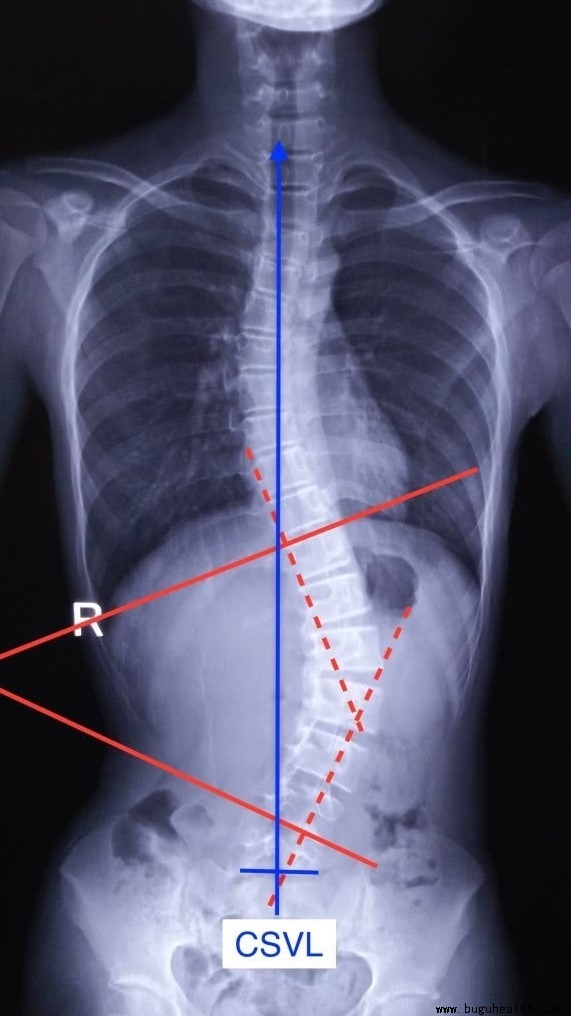

对于脊柱侧弯患者有专门的测量方法:Cobb角。

我们也可以用Cobb角的测量方法来测量脊柱矢状面的生理角度。

以胸椎为例:

第一步:确定要测量部位的端椎。上、下端椎就是指胸椎倾斜度最大的椎体,由于胸椎的生理曲度是向后凸的,通常上端椎是向前倾斜度最大,下端椎是向后倾斜度最大。

第二步:在上端椎的椎体上缘划一横线,同样在下端椎椎体的下缘划一横线。对此两横线各做一垂直线。

第三步:那么测量这两条直线的夹角就是 Cobb 角。

最后:依照正常脊柱侧生理曲度角度(颈椎30°-35°、胸椎20°-50°、腰椎40°-50°)来判断出被测量者的生理曲度是否正常: